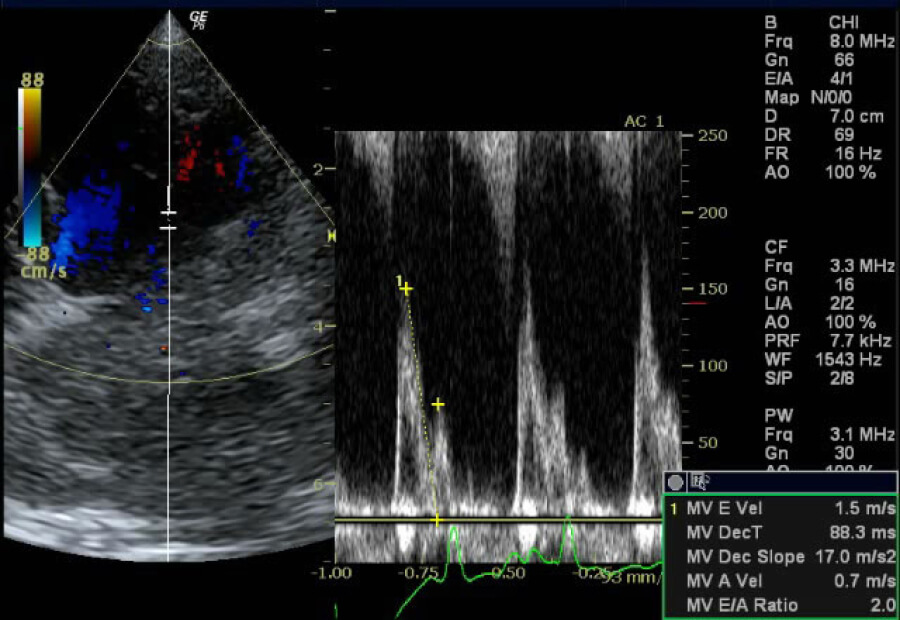

心エコー検査

超音波という“音”をあて、返ってくる反射波(エコー)を使って心臓を輪切りに画像化し、心臓の内部の状態を観察する検査です。動物の体への負担もほぼなく(*)、動き続ける心臓の様子をリアルタイムで観察できることから、心機能検査の中で最も重要な検査と言えます。

異常が起こっている箇所の血流の状況確認(逆流、狭窄、短絡など)や、正常もしくは異常な血流速度の計測、心筋の厚さの計測、心臓内圧の推測などを行います。心臓内に異常構造物を発見した場合はその形状なども詳しく探査します。

検出感度が高い検査であるため病変部を特定することが可能であり、重症度の判定や投薬の必要性の有無など、様々な判断場面で役立つ検査です。